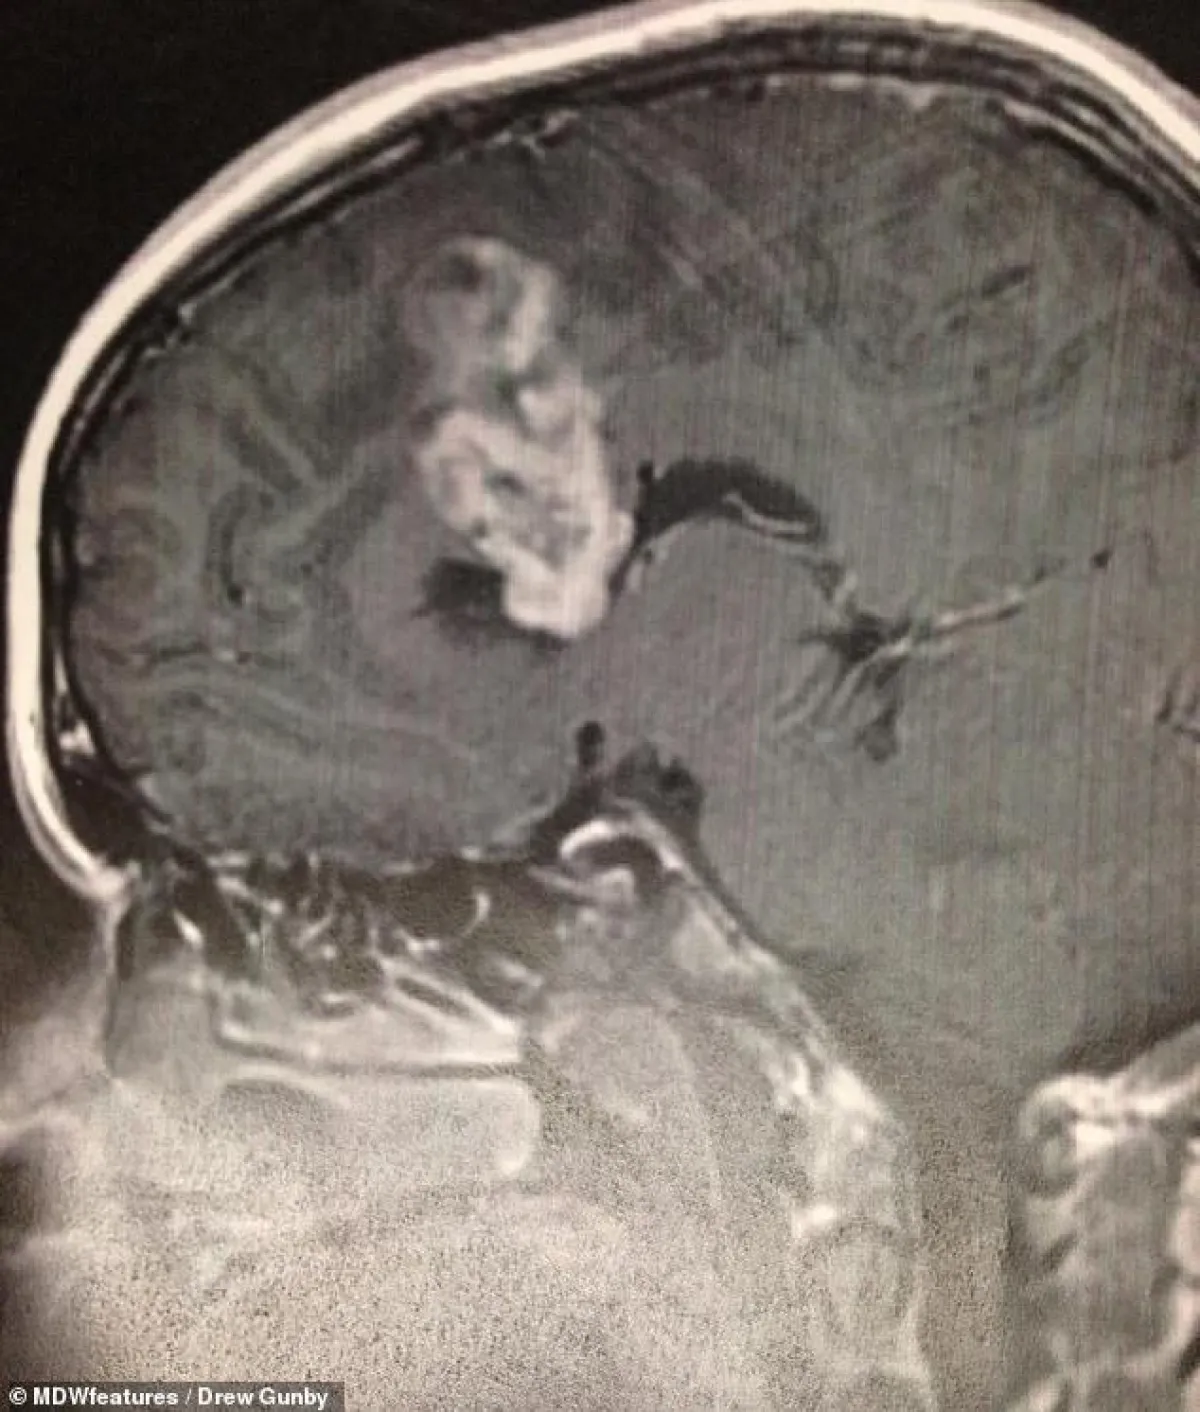

حادث سير لشاب تكشف له إصابته بورم سرطاني بالمخ؛ حيث تعرض طالب لحادث مأساوي في سيارة كان راكبًا فى المقعد الخلفي بها؛ حيث تم نقله على إثرها إلى المستشفى، وعند قيام الفريق الطبي بالفحوصات والأشعات له، اكتشفوا إصابته بورم في المخ، وبحسب موقع «ديلي ميل»، تم نقل «درو جونبي» البالغ من العمر21 عامًا من ولاية تكساس إلى المستشفى، بعد أن تعرض لحادث انقلاب سيارة، عندما فقد سائق السيارة التحكم فيها، وكان «جونبي» هو الشخص الوحيد الذي احتاج إلى علاج لوجود قطع في رقبته، وعند وصوله إلى المستشفى، أرسله الطاقم الطبي لإجراء أشعات وفحوصات أخرى؛ للتحقق من عدم وجود أي ضرر داخلي، وتبين من الأشعات أن «جونبي» يعيش بورم يبلغ طوله خمسة سنتيمترات ونصف في مخه، والذي كان موجوداً معه منذ عامين، وقام الجراحون بإجراء عملية جراحية لـ«جونبي» لإزالة الكتلة السرطانية؛ فلولا هذا الحادث، ما كان لـ«جونبي» ليعرف أنه يحمل ورماً سرطانياً في مخه، وسيستمر هذا الورم في النمو والتضخم حتى يقضي عليه.

ليس من الواضح نوع الورم الدماغي الذي يعاني منه «جونبي»، ولكن هناك حوالي 120 نوعًا مختلفًا من أورام المخ والجهاز العصبي المركزي، وعلى الرغم من أن شفاءه كان صعبًا في ذلك الوقت، إلا أنه كان يتقبل العلاج ولم يتركه مع أية تعقيدات دائمة، ولديه مسح بالرنين المغناطيسي منتظم لمتابعة حالته.